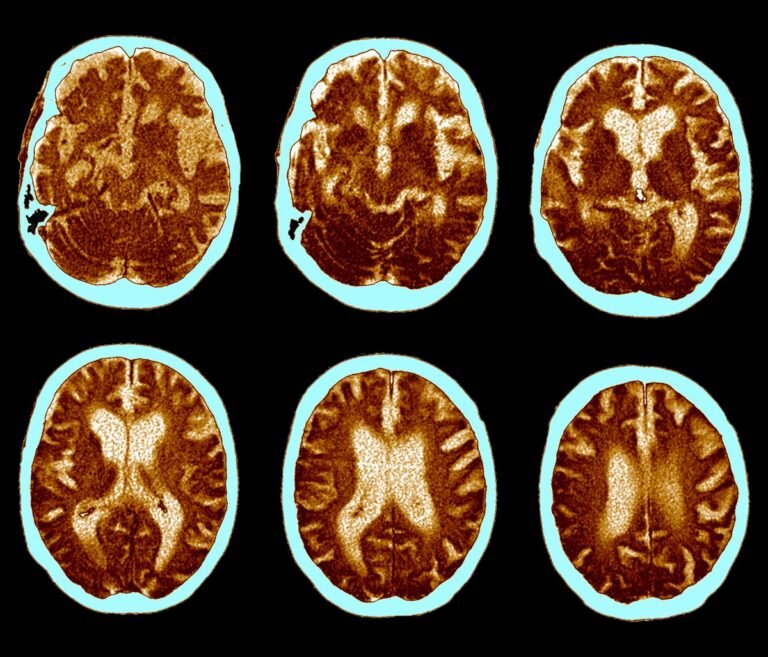

Brain CT scans of Alzheimer’s disease.